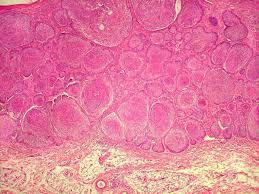

Anatomia Patológica

Exames disponíveis